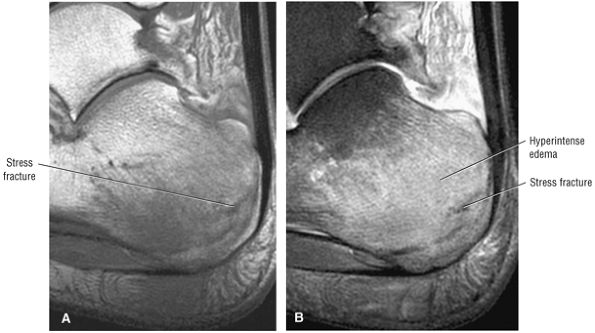

Stage I: Subchondral trabecular compression. Radiograph results are negative, bone scans are posi-tive, and marrow edema is seen on MR imaging (Fig. 5.95).

-